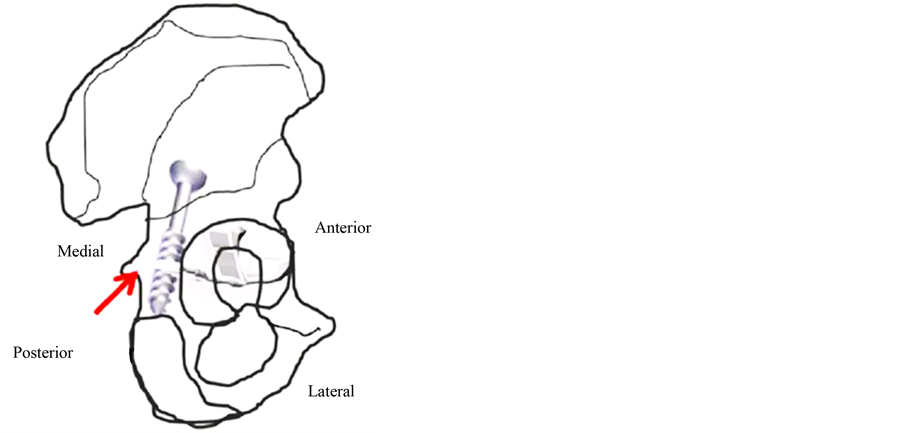

Figure 1. (a) A posterior oblique view of the coxis. The triradiate cartilage is marked and the red arrow identifies the area where the 2.7-mm cannulated screw was placed for the selective epiphysiodesis to the extraarticular portion of the ilioischialarm. (b) Percutaneous placement of a 2.7-mm cannulated screw under imaging intensifier.

Our hypothesis is that residual dysplasia may be improved by provoking selective growth arrest of the ilioischial arm of the triradiate cartilage (posterior epiphysiodesis). The aim of this study was to assess the possibility to obtain morphological changes in the acetabulum through posterior epiphysiodesis to the triradiate cartilage by the percutaneous placement of a 2.7-mm cannulated screw under imaging intensifier guidance in a pilot-model, experimental study in rabbits (Figure 1(a), Figure 1(b)).

A pilot study was conducted in 3-week-old New Zealand (number of animals: 20, 10 males and 10 females) rabbits submitted to unilateral surgery in one hip while the contralateral hip of the same group was used as a control. The operative side was chosen by random allocation. Posterior selective epiphysiodesis of the ilioischial arm of the extra articular portion of the triradiate cartilage was performed guided by an imaging intensifier using a 2.7-mm cannulated screw at three weeks of life (Figure 1(a), Figure 1(b)).